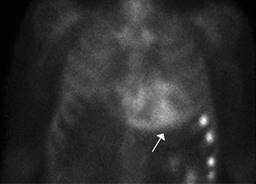

A transthoracic echocardiogram revealed a dilated left ventricle with end-diastolic diameter 60 mm, mild to moderate septal hypertrophy and severely depressed systolic function (20% LVEF by Simpson) due to global hypokinesia. He also had biatrial dilatation, a severely dilated right ventricle with depressed systolic function, mild regurgitation of the four heart valves, mild pulmonary hypertension and dilated inferior cava vein. A cardiovascular magnetic resonance (CMR) showed biventricular dilatation and systolic dysfunction (Figure 1A). High native T1 values (1304 milliseconds) and an increase in extracellular volume (40 with a 43.2% hematocryte) were reported and T1 PSIR sequences disclosed epicardic mid inferolateral, inferoseptal, subendocardial anterior and anterolateral late gadolinium enhancement (Figure 1B). These findings were compatible with infiltrative cardiomyopathy and suggestive of cardiac amyloidosis. At this point, a 99mTc-DPD bone scintigraphy, a blood and urine analysis to evaluate a possible monoclonal component -according to the latest recommendations on the diagnosis of cardiac amyloidosis4 and cardiac catheterization were requested. ATTR cardiomyopathy compatible images were reported in the scintigraphy with a significant Perugini grade 3 heart uptake of the radiotracer (Figure 2). The coronary angiography showed only mild irregularities in the left anterior descending and circumflex coronary arteries without significant obstructive lesions. The search for light chain immunoglobulin monoclonal gammopathy was negative, AL amyloid heart disease was ruled out, so ATTR cardiomyopathy was diagnosed.

Figure 2: 99mTc-DPD scintigraphy: intense cardiac uptake (arrow) of the radiotracer is observed in both ventricles (Perugini score 3), with mild diffuse bone uptake that is higher in the broken left ribs.